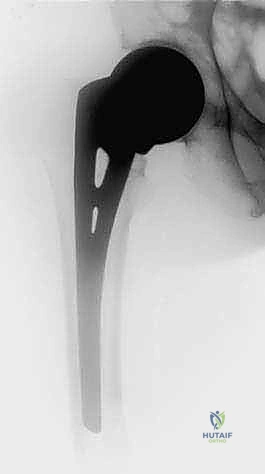

2. استئصال الورم وتغيير المفاصل (Tumor Resection & Endoprosthetic Arthroplasty)

في الحالات التي يدمر فيها الورم المفصل بالكامل (مثل مفصل الورك أو الركبة)، يقوم الدكتور هطيف باستئصال الجزء المصاب من العظم والورم معاً، واستبداله بمفصل صناعي خاص بالأورام (Megaprosthesis). بفضل خبرته الواسعة في تغيير المفاصل، يستطيع المريض المشي في اليوم التالي للعملية!

| عظم الفخذ (القسم العلوي) | كسر عنق الفخذ، العجز عن المشي. | استبدال مفصل الورك بمفصل صناعي (Arthroplasty). |